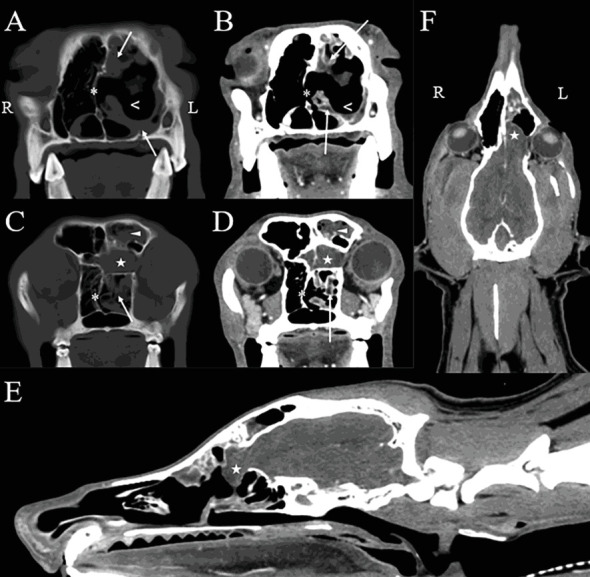

一只4岁雄性阉割混血狗被田纳西大学兽医学院兽医中心收治,以评估单侧鼻分泌物。患者出院已有2个月,在转诊前6周由兽医经验性治疗后,病情由脓性发展为出血性。狗有癫痫发作的历史,从1岁开始,用苯巴比妥控制。头部的计算机断层扫描和磁共振成像诊断为左侧脑膜脑膨出,嗅球延伸至鼻尾通道,伴有曲霉菌病的破坏性鼻炎和额窦炎。进行鼻镜检查以收集诊断样本,清除真菌斑块,并指导克霉唑乳膏的应用。活检显示化脓性鼻炎伴大量曲霉病,真菌培养证实为曲霉属。术后给予短疗程口服泊沙康唑治疗。治疗后4个月出现剧烈呼吸。复查鼻窦镜和鼻镜发现左鼻腔有一个真菌斑块,鼻甲小,充血。反复治疗,临床症状得到缓解。1个月后复查鼻镜未见残留病变。癫痫在第二次治疗后3年复发,由初级保健兽医进行医学处理。这个病例报告描述了一个罕见的病例鼻曲霉病并发脑膜膨出。尽管大筛网板缺损导致脑膜和嗅球暴露,但该患者对反复清创和局部抗真菌治疗耐受良好。3年无复发迹象,此后犬失去随访。

A 4-year-old male castrated mixed breed dog was admitted to the Veterinary Medical Center of the University of Tennessee College of Veterinary Medicine for evaluation of unilateral nasal discharge. Discharge had been present for 2 months, with progression from purulent to hemorrhagic discharge after empiric treatment by the primary veterinarian 6 weeks prior to referral. The dog had a history of seizures starting at 1 year of age that were controlled with phenobarbital. Computed tomography and magnetic resonance imaging of the head yielded diagnoses of a left-sided meningoencephalocele with extension of the olfactory bulb into the caudal nasal passage and destructive rhinitis and frontal sinusitis consistent with aspergillosis. Rhinoscopy was performed to collect diagnostic samples, debride fungal plaques, and guide clotrimazole cream application. Biopsies revealed suppurative rhinitis with abundant aspergillosis, with Aspergillus sp. confirmed on fungal culture. Postoperatively, the patient was treated with a short course of oral posaconazole. Stertorous breathing was noted 4 months following treatment. Recheck sinoscopy and rhinoscopy revealed one fungal plaque in the left nasal cavity and small, hyperemic turbinates. Treatment was repeated, resulting in resolution of clinical signs. Repeat rhinoscopy 1 month later had no evidence of residual disease. Seizures recurred 3 years after the second treatment and were medically managed by the primary care veterinarian. This case report describes a rare case of nasal aspergillosis complicated by a meningoencephalocele. Despite the large cribriform plate defect resulting in exposure of the meninges and olfactory bulb, repeated debridement and topical antifungal treatment were well tolerated by this patient. There was no recurrence in signs for 3 years, after which the dog was lost to follow-up.